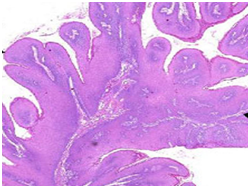

Histopathological statutes: The squamous epithelium displays finger like projections, the epithelial maturation pattern is orderly with epithelial hyperkeratosis. Spinous epithelial cells may depict cytoplasmic vacuolation with pale, clear perinuclear haloes, nuclear pyknosis and infrequent basilar hyperplasia. Oral squamous papillomas frequently display koilocytosis on account of the co-existent cytopathic influence. Atypical nuclear alterations may be exemplified; particularly with immune-compromised (HIV positive) individuals.9 The epithelium displays a typical maturation pattern with prominent hyperkeratosis. Epithelial to basal cell quantification is moderate (basilar hyperplasia) along with an extensive koilocytic transition.1 Virally induced carcinomas are the poorly differentiated, non-keratinizing tumours and may be enunciated in the tonsils of sexually active young men. Majority of the tumours elucidate the p16 proteins. Oro-pharyngeal cancers which are reactive for human papilloma virus (HPV) frequently depict basaloid morphology. Apart from a viral genesis, squamous papillomas may ensue from mechanical irritation or may be genetically determined as a constituent of Cowden’s syndrome.

Figure 6 Squamous papilloma- oesophagus.

Figure 7 Papillomas with buried epithelial glands.